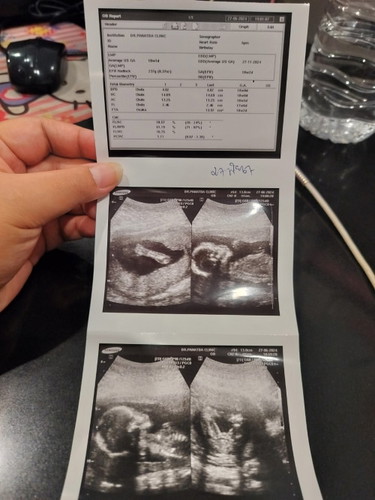

ไปอัลตร้าซาวด์ 2 รอบ หมอบอกไม่มั่นใจ แต่น่าจะผู้หญิง ทั้ง2รอบเลยค่ะ แต่คนทักว่าได้ผู้ชาย ตอนนี้อายุครรภ์ 26 วีคแล้วค่ะ ยังไม่ได้ไปซาวด์อีกรอบเลย แม่ๆช่วยดูหน่อยค่ะ ว่าหญิงหรือชายคะ